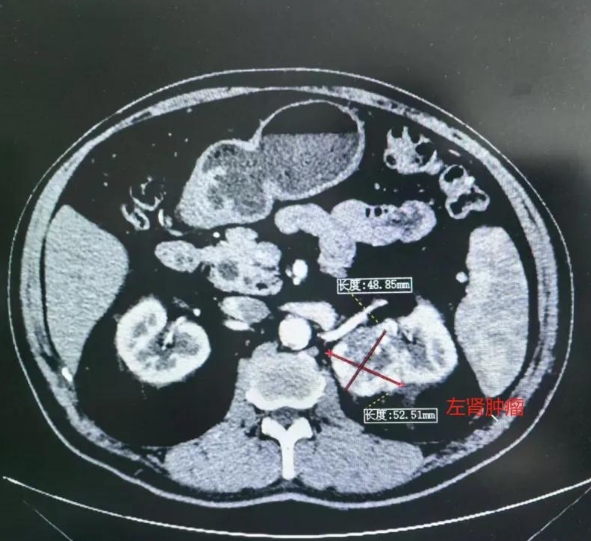

肾脏增强CT

集团泌尿外科专家团队研究患者病情,由于该例患者的肿瘤位于左侧肾门部,偏肾上极内侧,肿瘤最大直径约52mm,紧贴左肾动脉,属于特殊部位的肾脏肿瘤。并且,患者身体素质较差,有多年的糖尿病、慢性肾衰竭、冠心病心脏支架置入术、肺脓肿病史,行保留肾单位的肾部分切除术,可能会因术中出现血管损伤、完整切除肿瘤困难等情况,更改手术方式为肾根治性切除,保肾难度及手术风险较大,如保肾不成功,患者将失去更多的肾单位,肾衰病情可能会进一步加重,因此,患者的保肾需求及意愿极其强烈。